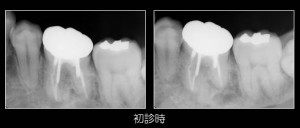

レントゲン写真は、このような感じ。よくある隙間がありそうな根の詰め物・・・。